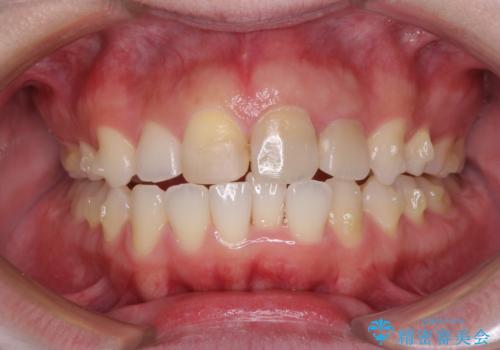

抜歯矯正の後戻り インビザラインによるオープンバイトの再矯正

- 以前矯正治療をされていましたが、後戻りが起きたことを気にして来院された患者様です。

上下前歯のオープンバイトを改善するため、インビザラインにて治療を行うこととしました。